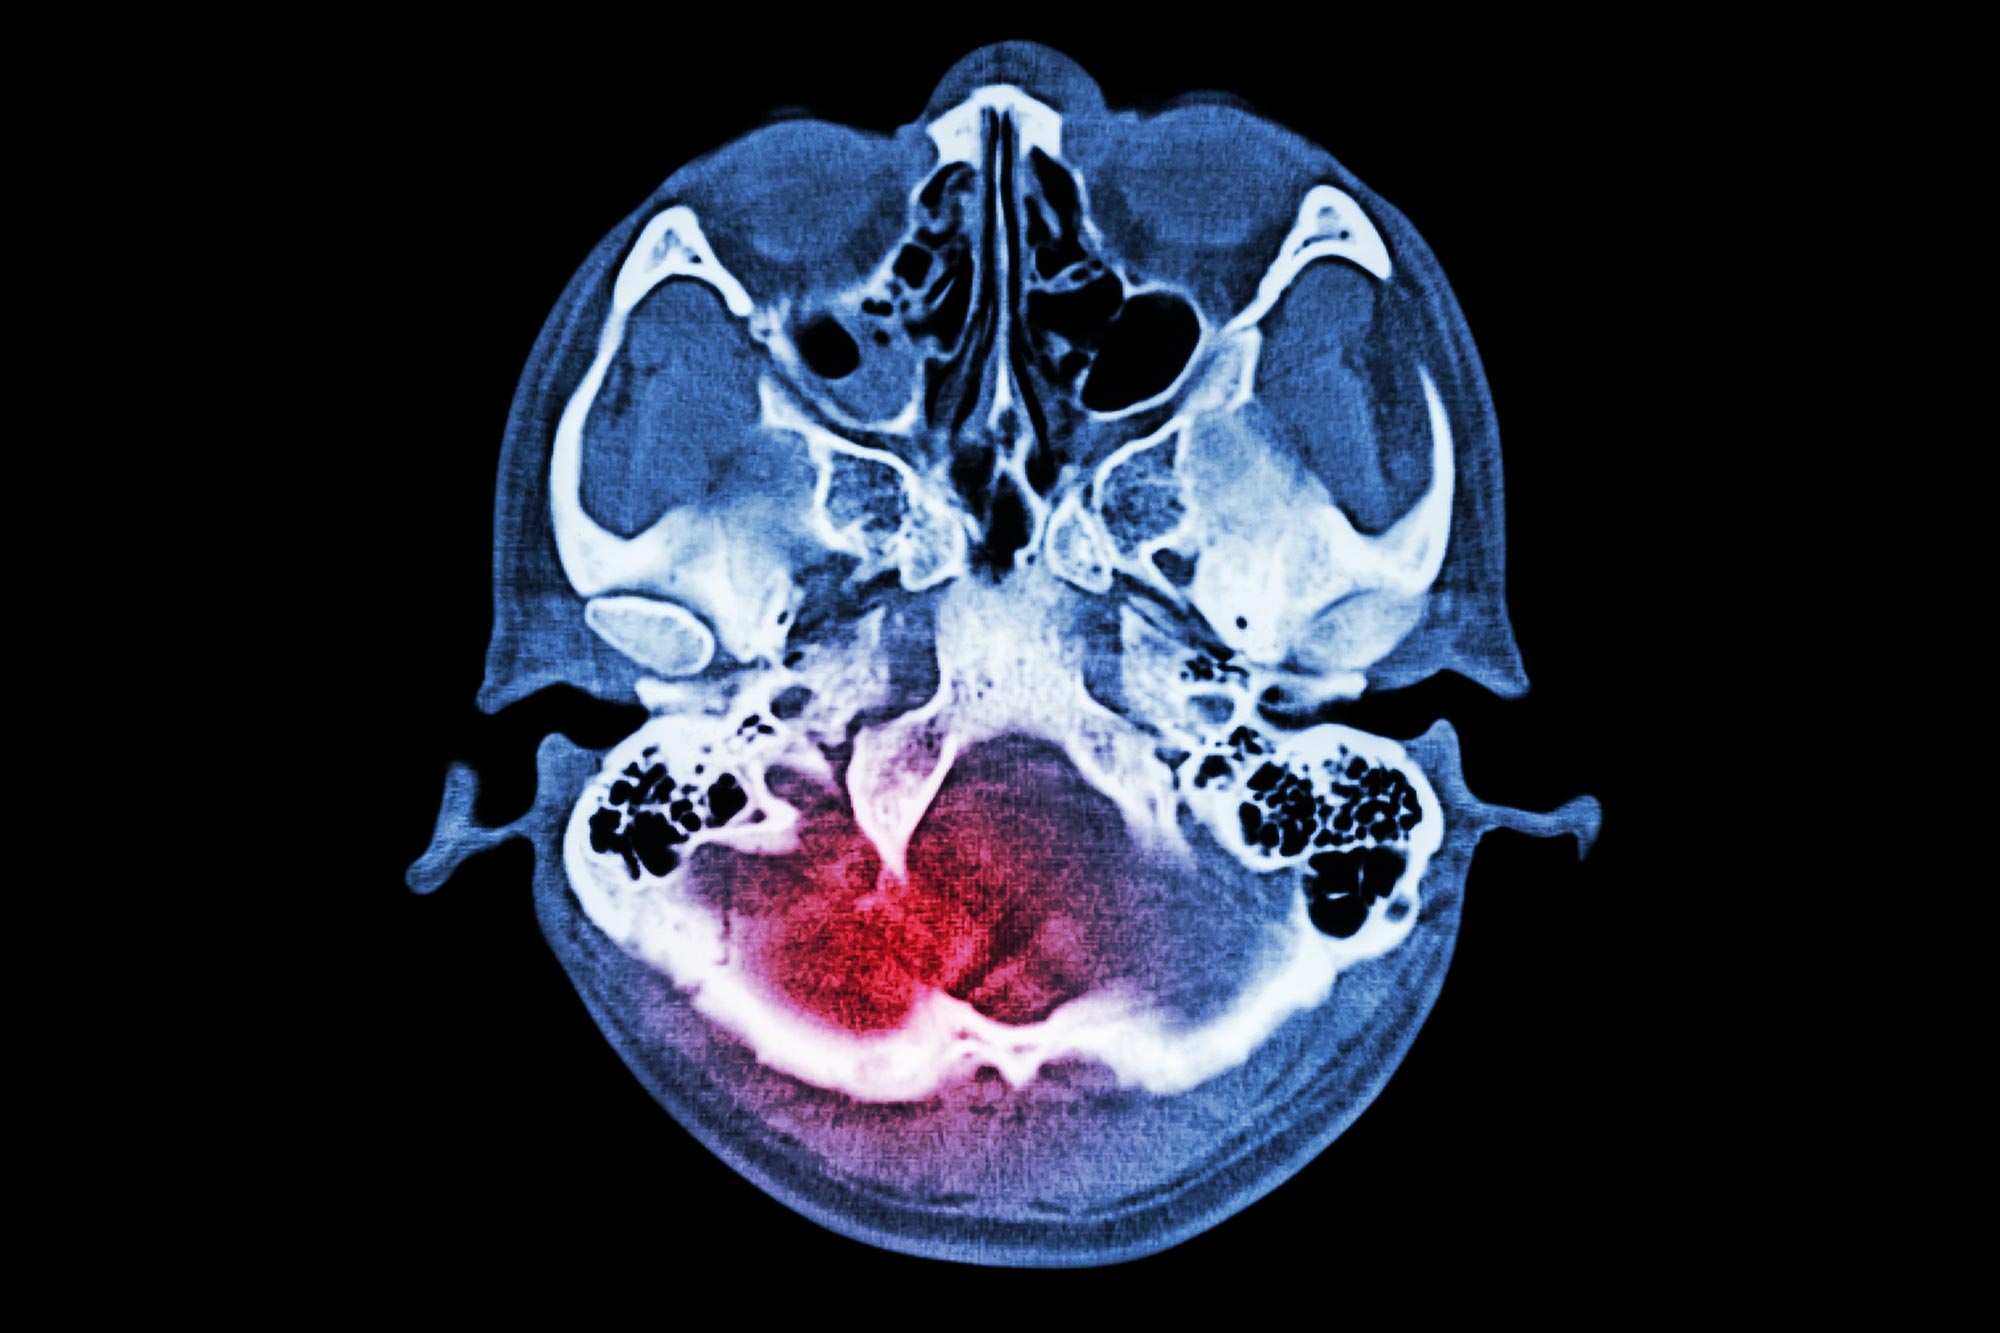

שבץ איסכמי מתרחש כאשר זרימת הדם לחלק מהמוח מופסקת, מונעת מתאי המוח חמצן וחומרי מזון. ללא טיפול בזמן, תאי המוח עלולים למות, וכתוצאה מכך נזק קבוע למוח ולתפקודיו. שבץ מוחי הוא אחד מגורמי המוות והנכות המובילים בעולם, המשפיע על מיליונים מדי שנה.

אחד האשמים העיקריים מאחורי נזק מוחי שנגרם לשבץ הוא א נוירוטרנסמיטר שנקרא גלוטמט. כאשר המוח מורעב מחמצן וסוכר, רמות הגלוטמט עולות בצורה דרמטית, ומעוררת יתר על המידה קולטני N-methyl-Daspartate (NMDARs) על הממברנה של תאי המוח. זה גורם לגל של סידן לחדור לתאים, וגורם למפל של אירועים שבסופו של דבר מובילים למוות של תאים.